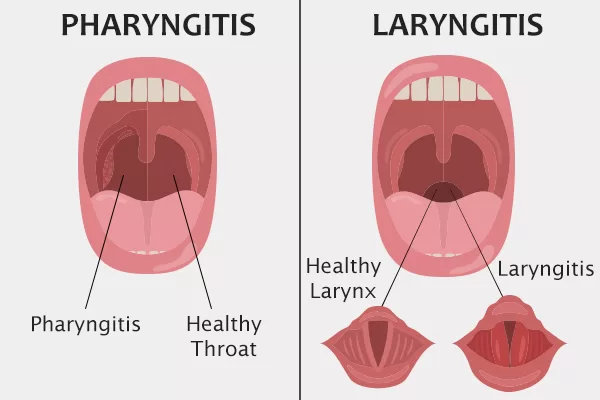

3. Faringitis dan Laringitis

Faringitis merupakan peradangan pada faring sehingga timbul rasa nyeri pada waktu menelan ataupun kerongkongan terasa kering. Gangguan ini disebabkan oleh infeksi bakteri atau virus dan dapat juga disebabkan terlalu banyak merokok. Bakteri yang biasa menyerang penyakit ini adalah Streptococcus pharyngitis.

Laringitis mengakibatkan penderita serak atau kehilangan suara. Penyebab laringintis antara lain karena infeksi, terlalu banyak merokok, minum alkohol, dan terlalu banyak serak.